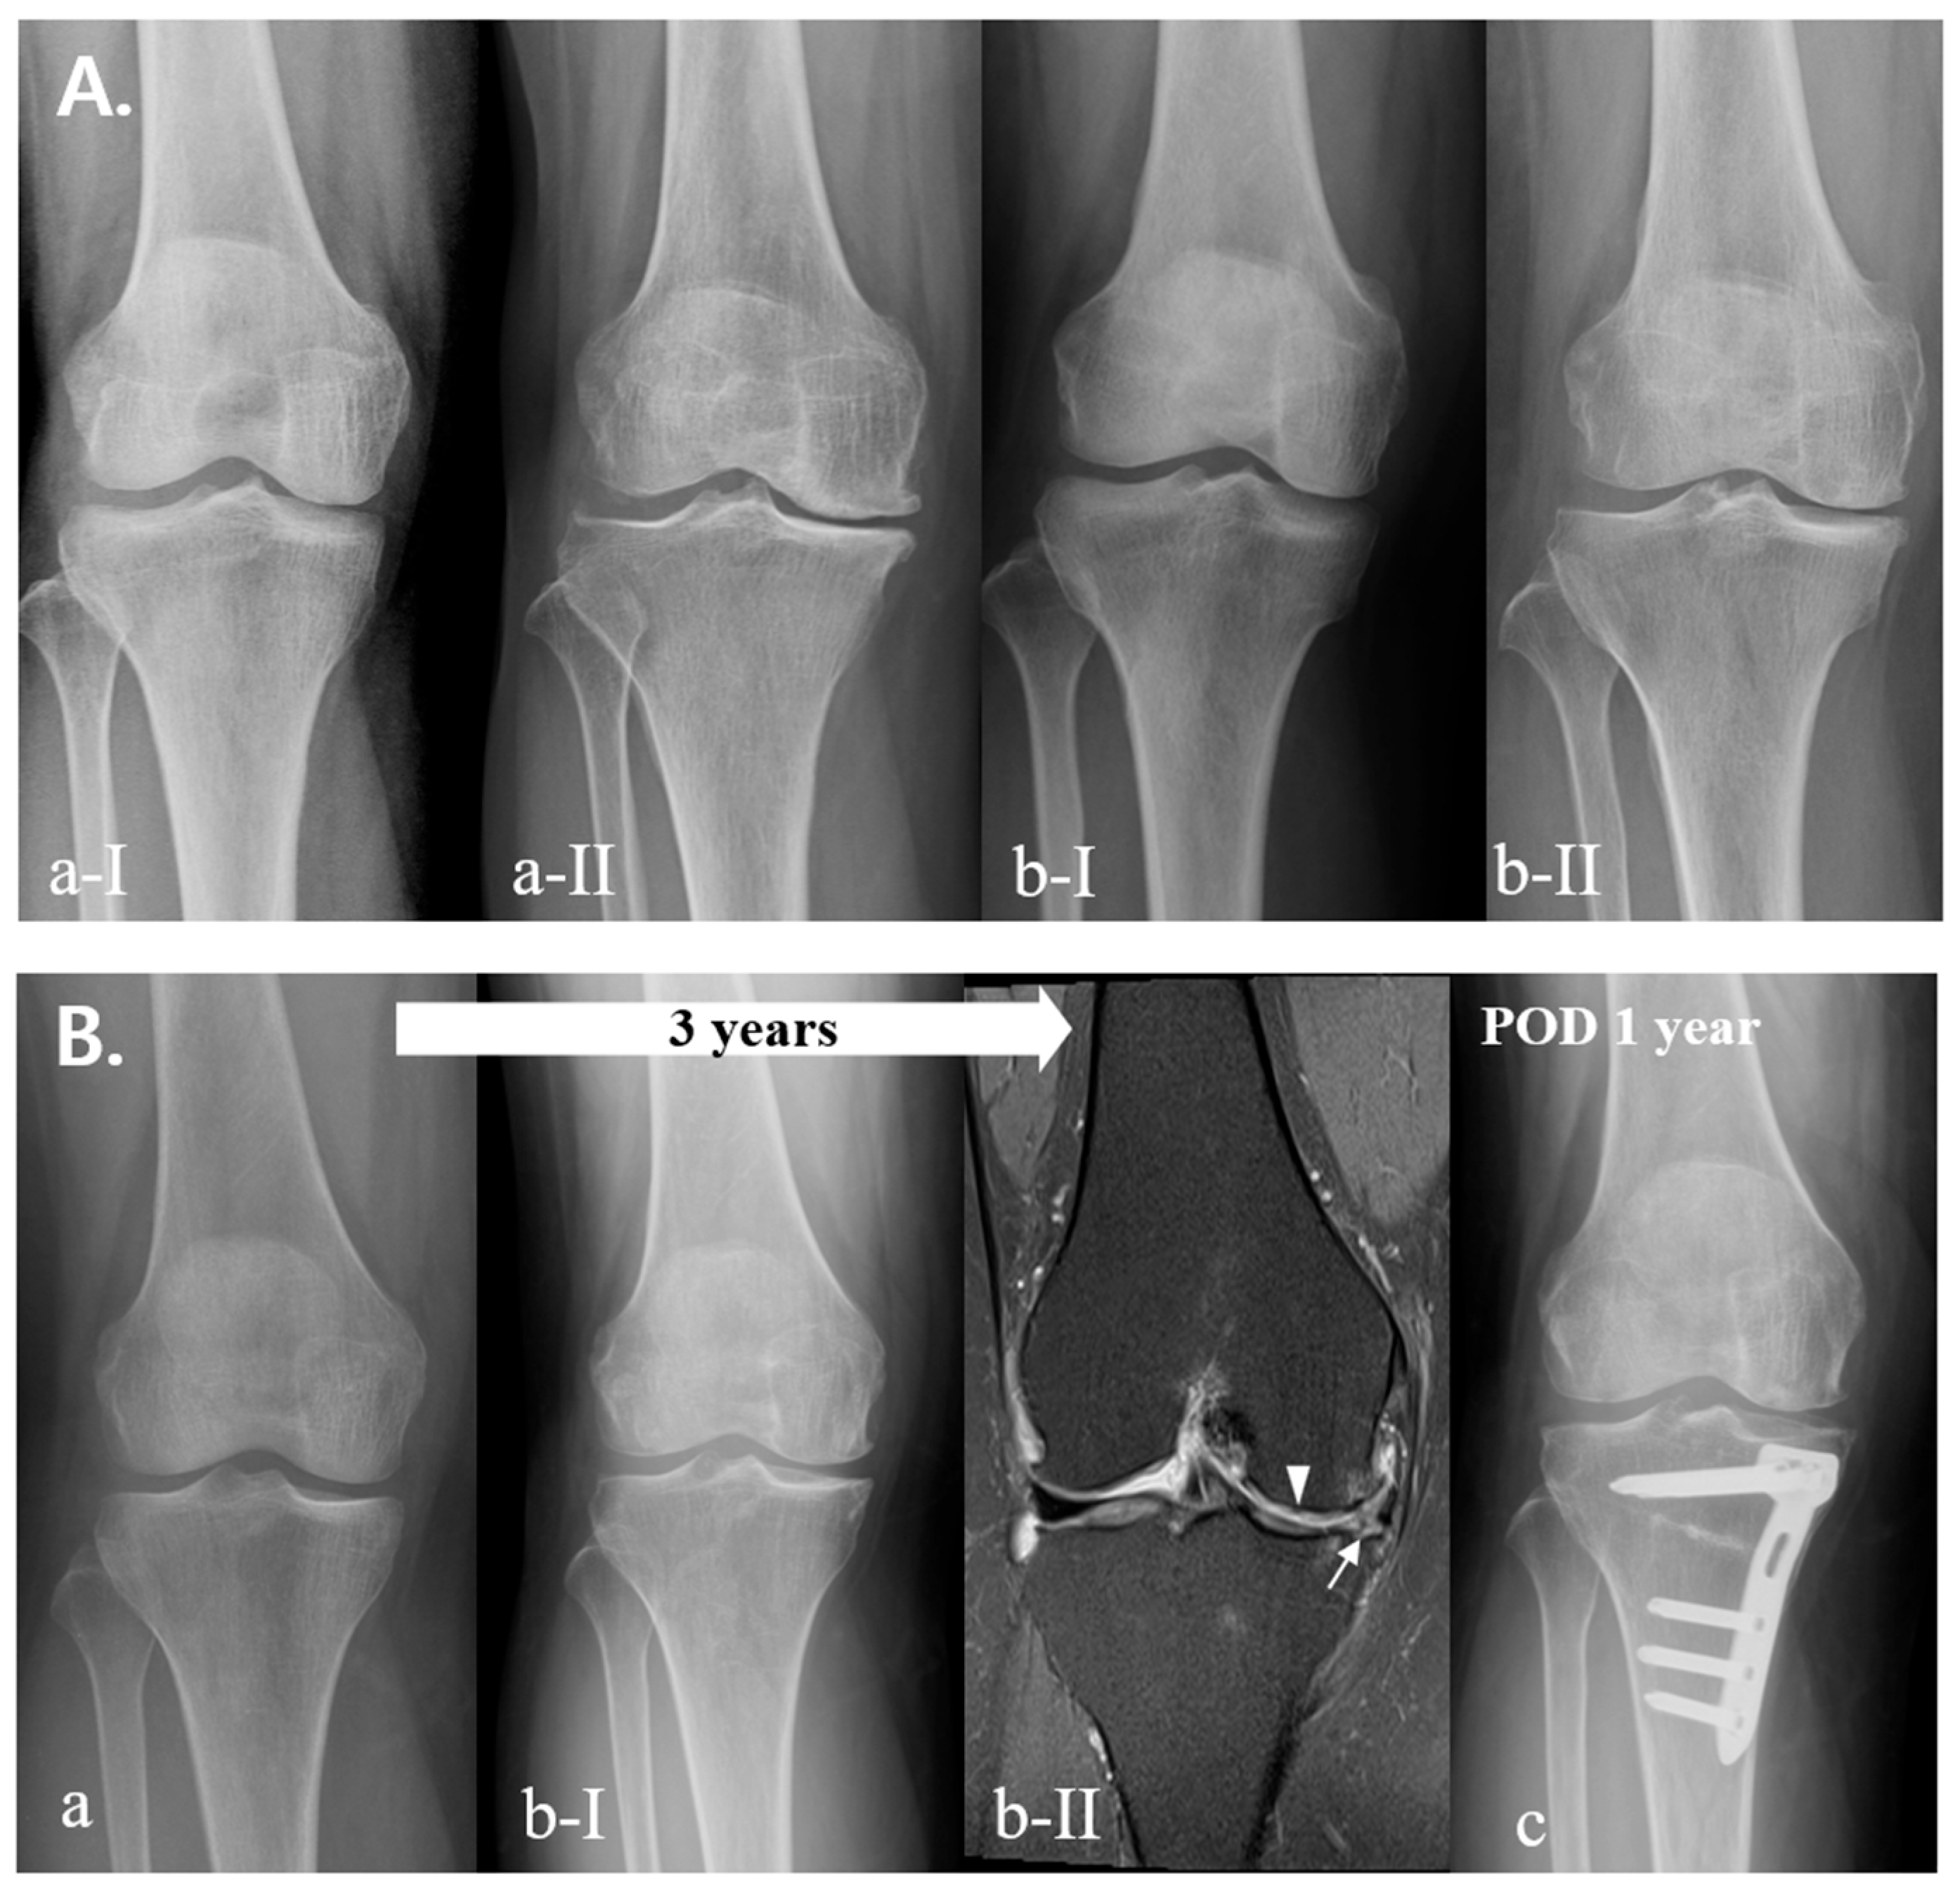

3. Results